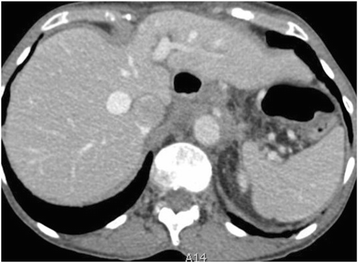

Visceral metastases

True haematogenous parenchymal metastases are extremely rare at presentation. Invasive serosal surface implants are the most frequent mode of parenchymal involvement of liver and spleen and these may invade the underlying liver parenchyma. Surface hepatic implants can be easily strummed at surgery whilst deeply invasive implants require partial segmental or lobar hepatectomy and the extent of surgical resection requires pre-operative liaison with hepatobiliary surgeons. Implants in Morrisons pouch extending to hepatic porta and IVC are said to increase the risk of sub optimal resection and intraoperative bleeding [Fig. 9].

Fifty-five year old woman with endometriod carcinoma of the ovary. Hepatic subcapsular deposits (arrows) with invasion of underlying liver parenchyma (dashed arrows). The invasion requires hepato-biliary surgical assistance as segmentectomy or lobectomy may be required in patients being considered for optimal resection